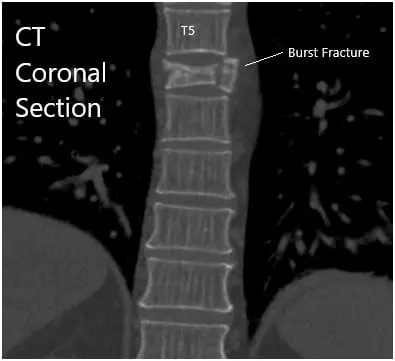

CT revealed moderate acute wedge compression fracture associated with the T6 vertebral body. The posterior cortex of the T6 vertebral body mildly impresses upon the anterior margin of the thoracic dural sac. Minimal hematoma is situated between the T6 vertebral body and the surrounding pleura.

There was a normal configuration of the remaining thoracic vertebral bodies. The thoracic disc spaces are not narrowed. Posterior disc bulges or herniations are not demonstrated. The narrowing is not associated with the thoracic neural foramina.

CT Sagittal and coronal Sections.